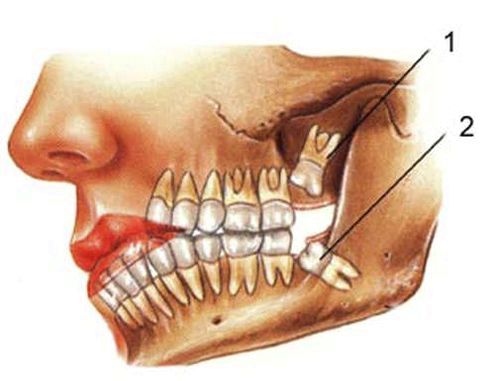

Ретінірованний зуб: що це і чим

Так, прийнято розрізняти карієс:

- Між жувальними зубами. Найбільше люди страждають саме від цього виду карієсу. Своєю частотністю він зобов'язаний великому навантаженні на жувальні зуби

- Між передніми зубами. Він доставляє набагато більше клопоту своєму власникові, ніж карієс між жувальними зубами, так як саме передні зуби видно всім. А в той момент, коли на них утворюється карієс, зуби стають більш сірими, а також можливі поява чорних ділянок

- Між молочними зубами. Даний вид карієсу розвивається зазвичай після чотирьох років. Існує думка, що молочні зуби лікувати не обов'язково, так як вони все одно випадуть. Це помилка, тому що зараження молочного зуба може призвести до потрапляння інфекції в зачатки постійних зубів, а як наслідок, зіпсовані корінні зуби

- Збоку зуба. Це випадок зустрічається е часто. Це так звана стадія, коли один зуб уражений, а інший залишається повністю здоровим, тобто мікроби не встигли його зруйнувати